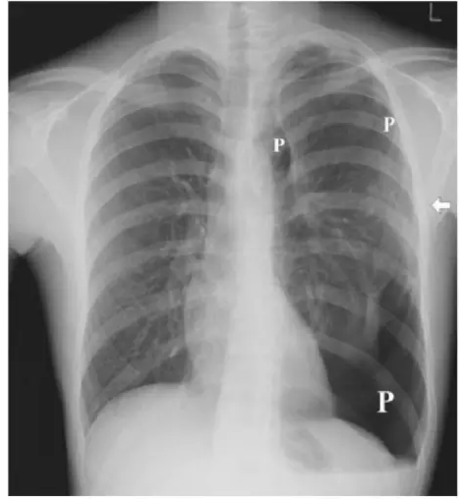

照片名称:液气胸

x线正及侧位透视和拍片可协助诊断,可见萎陷之肺边缘即气胸线,压迫性